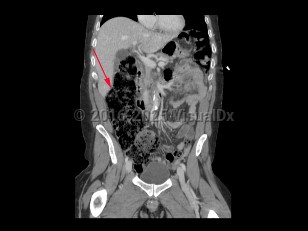

- Give fluid resuscitation to patients presenting with hypovolemia or signs of shock, with pressors as needed.

- Obtain urgent surgical consultation and administer early antibiotics for patients presenting with signs of bowel ischemia or sepsis.

- Provide symptomatic therapy with intravenous (IV) pain medication and antiemetics.

- Give the patient nothing by mouth.